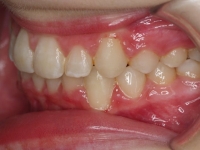

El paciente A.J. de 11 años, acude a nuestra consulta con apiñamiento maxilar importante. El canino lateral (12) está en mordida cruzada. Presenta una Clase II molar y canina, y la línea media está desviada. Se realizó un tratamiento con brackets autoligables metálicos de smartclip 022. La duración del tratamiento fue de 22 meses.